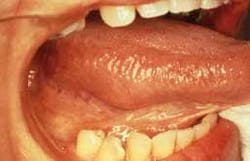

Intraoral examination revealed a large swelling on the right lateral tongue (see photo). Palpation of the area revealed a soft, well-circumscribed nodule that measured approximately two centimeters in diameter. The mass was described as non-painful when compressed. Further oral examination revealed no other lesions present.